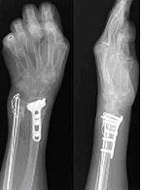

若不幸發生了骨折的狀況,仍需要接受手術治療,否則便有可能因為骨折而痛苦不堪或長期臥病在床了。目前骨質疏鬆性骨折的手術由於科技的進步,陸續研發出新型的骨釘骨板,它們都至少包括以下一個或多個特點:

1.鎖定式設計;2.符合骨頭解剖學上的形狀;3.可以微創手術方法進行;4.以鈦合金製成,較符合骨頭的物理特性。

以鎖定式骨釘骨板為例,螺絲頭及骨板上都有螺紋,可以將螺絲直接鎖定在骨板上,使骨折的固定更堅固,不像傳統的設計,螺絲容易鬆脫,如此針對骨質疏鬆患者,可以得到較好的固定;對於靠近關節的骨折,可使用關節預先鑄型骨板系統,減少傳統骨板不易塑形的缺點;若加上以微創方法進行手術,將開刀傷口減至最小,可大幅減少軟組織破壞,骨折的血液循環不至被破壞將可使骨折的癒合速度加快。雖然骨折手術方法日漸進步,但是預防仍舊勝於治療,增加骨本與預防跌倒仍然是最重要的課題。